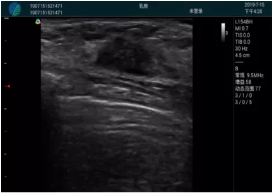

清晰顯示腺體內(nèi)低回聲快影,邊界清晰,包膜較光滑

確定進(jìn)針路徑并實(shí)時(shí)監(jiān)測(cè)抽吸針與腫塊位置關(guān)系

抽吸針進(jìn)入腫塊內(nèi)部進(jìn)行旋切

抽吸過程中可見腫塊明顯縮小,并根據(jù)腫塊位置改變針道位置

抽吸旋切后再進(jìn)行超聲復(fù)查,原腫塊區(qū)域未見殘留組織及出血

超聲引導(dǎo)下抽吸旋切取出的腫塊組織